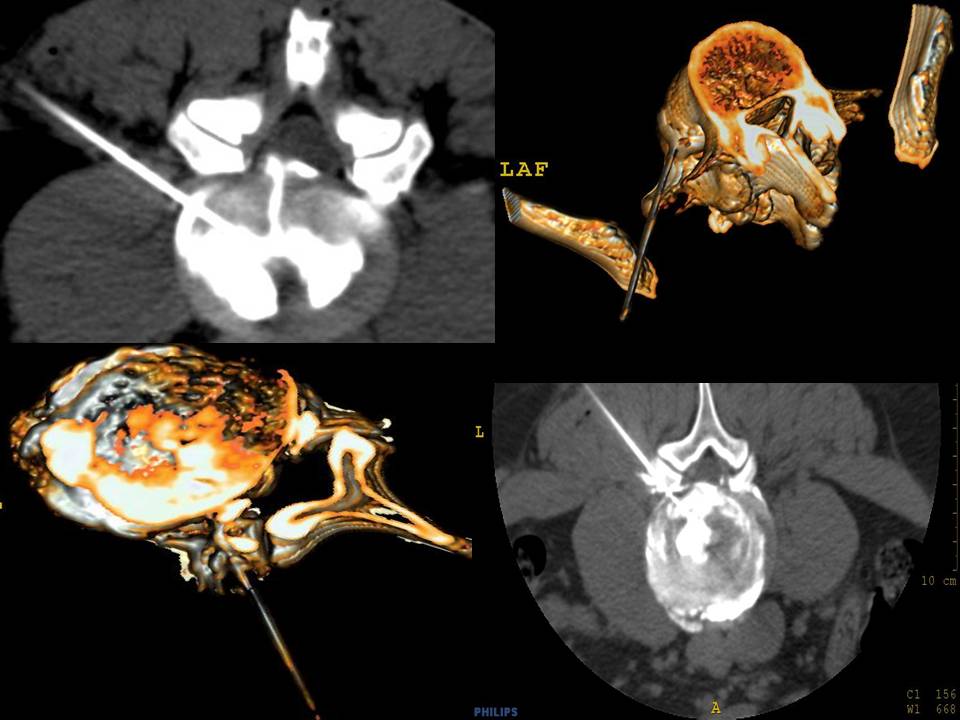

Cet examen est réalisé en ambulatoire chez un patient ayant un bilan sanguin comprenant une numération de la formule sanguine, un bilan d’hémostase (TP, TCA, plaquettes), et un bilan inflammatoire (VS, CRP).Le patient doit être accompagné pour son retour à domicile.Dans notre service nous disposons d’un scanner et d’un arceau de scopie (figure 1), l’ensemble de la procédure est donc réalisée sous double guidage pour des raisons de commodité. Cependant, la première étape diagnostique peut être réalisée sous scopie seule puis passage du patient au scanner pour l’analyse morphologique du disque. Le patient est positionné en décubitus ventral avec mise en place d’un billot abdominal pour diminuer la lordose lombaire.Une désinfection par chaine bétadinée est réalisée sur l’ensemble de la zone à explorer. Nos patients ne sont pas sédatés de façon à pouvoir répondre précisément aux questions posées pendant l’examen.Le point de ponction est toujours contro-latéral à la douleur ressentie par le patient afin de diminuer les faux positifs. La voie d’abord est facile pour les disques de L1 à L5 : le point de ponction est à environ un travers de main de la ligne mediane, le niveau à explorer est localisé sous scopie (figure 2) (4) .Un scanner volumique permet de repérer l’émergence radiculaire et déterminer aisément l’angle de la voie d’abord (figure 3). Le scanner pré-discographie n’est pas obligatoire il facilite seulement le guidage. Sous scopie, le rayon de profil strict doit parfaitement aligner le disque à opacifier. Après anesthésie locale (xylocaine 1%) l’aiguille Chiba est positionnée latéralement parallèle au plateau vertébral supérieur de la vertèbre inférieure. L’aiguille progresse sous scopie itérative en passant par la portion inférieure du foramen afin d’éviter les structures nerveuses. L’angle d’approche est d’environ 45° par rapport à la ligne médiane (figure 2).

A l’étage L5-S1 l’approche peut se révéler plus délicate surtout en cas de disque encastré entre les crêtes iliaques obstruant le trajet de l’aiguille.La voie d’abord toujours parallèle aux plateaux vertébraux peut être plus haute que L4-L5 compte tenu de l’angulation de L5-S1 dans le plan sagittal (figure 5). Une acquisition volumique scanner avec reconstruction permet de facilement planifier le trajet de l’aiguille. Sous scopie, une angulation cranio-caudale permet de dégager un triangle formé par le plateau inférieur de L5, le processus articulaire supérieur de S1 et la crête iliaque, l’aiguille devant passer à travers ce triangle. Pour faciliter l’accès et la pénétration dans le disque l’aiguille pourra être courbée. (figure 4).Dans certain cas nous utilisons une voie postéro-médiane transdurale ou latéro-durale, le scanner permettant de déterminer une voie d’abord entre le sac dural, la racine et le disque (figure 6).Le contact de l’extrémité de l’aiguille avec le disque présente une résistance avec un aspect rénitent pouvant entrainer une douleur modérée (innervation des fibres de Sharpey) puis la progression dans le disque devient plus facile. La confirmation du bon positionnement de l’aiguille au centre du disque se fait par une coupe scannographique ou sous scopie par une incidence antéro-postérieure.Une deuxième aiguille est positionnée à un autre niveau considéré non pathologique pour servir de disque contrôle.L’injection de produit de contraste intra-discal débute rayon perpendiculaire au disque. Le patient n’est pas informé du niveau discal injecté. Nous commençons par le disque non pathologique afin d’évaluer le niveau de douleur et la tolérance du disque contrôle pour limiter les faux positifs (figure 7).L’injection se fait lentement à la seringue luer lock en repérant le volume injecté.